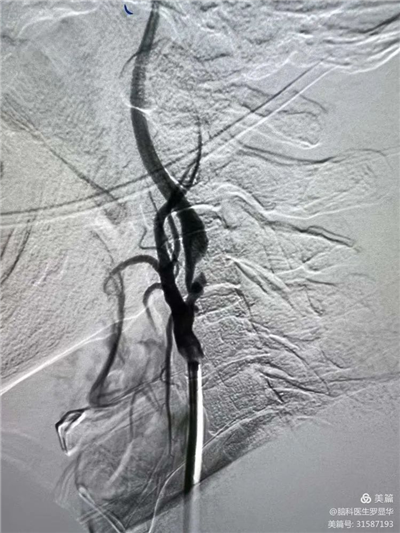

手術(shù)過程:指引導管到位

手術(shù)過程:球囊擴張后,protege支架到位

術(shù)后造影示狹窄解除